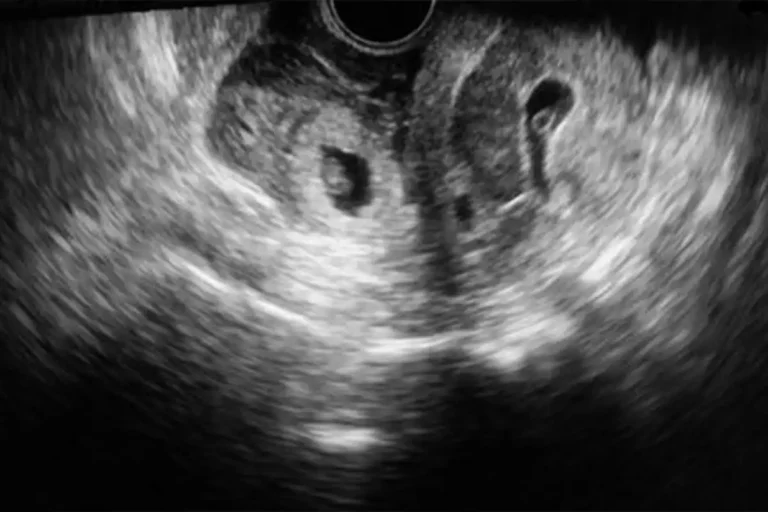

Heterotopik Gebelik Nedir? Heterotopik gebelik, nadir görülen bir durumdur ve bir kadının